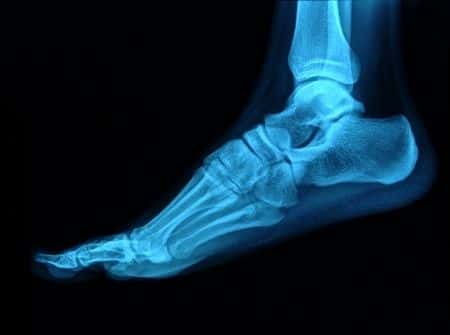

This case involves a patient who was admitted to the hospital for an elective total left hip replacement. After surgery, the patient complained of an inability to flex or extend their left ankle. The impression in the medical note was that there was a postoperative foot drop associated with numbness on the dorsal aspect of the foot. A neurology consult and further imaging studies were ordered to evaluate the possibility of any nerve damage from the surgery. An electromyography (EMG) showed a left sciatic mononeuropathy with the lesion predominantly affecting the peroneal fibers. Additionally, an MRI showed that there was a large neuroma formation of the sciatic nerve at the level of the femoral neck with surrounding scar encasement. The plaintiff claims that the surgeon lacerated this nerve, after the plaintiff consulted other surgeons who attribute the neuroma formation to a damaged nerve.